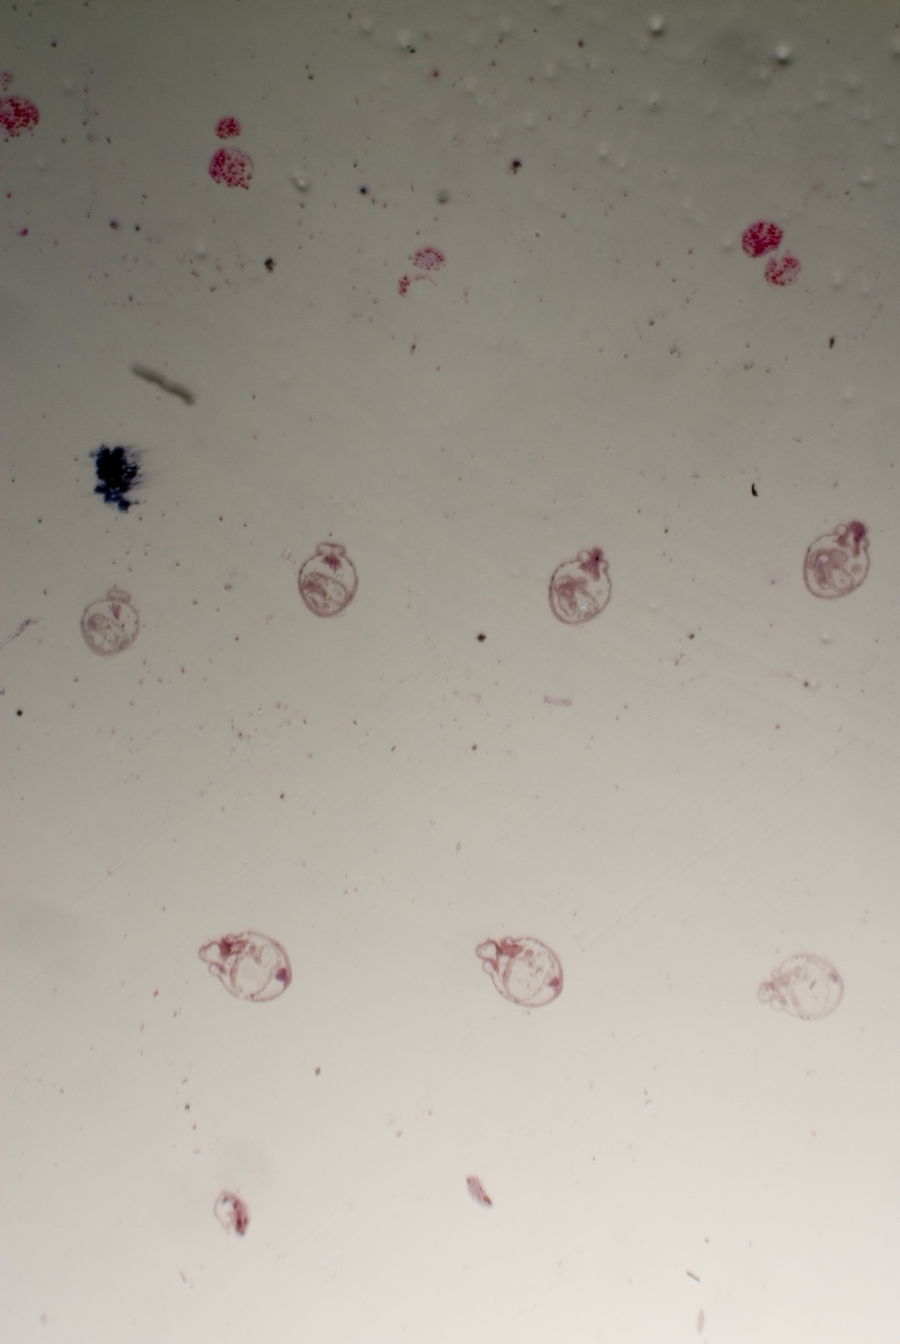

Image Filename: 50141_3896-1

50141_3896-1

container invno 50141

specimen id 3896